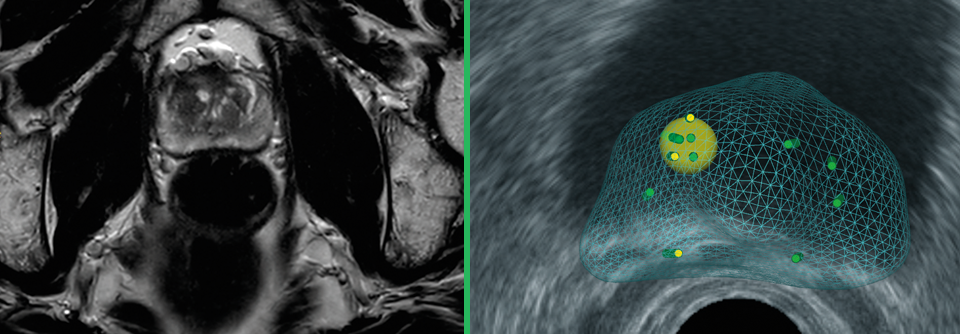

Wenn das mpMRT zum Einsatz kommt, muss eine Biopsie nur noch alle drei Jahre erfolgen. (Agenturfoto) Wenn das mpMRT zum Einsatz kommt, muss eine Biopsie nur noch alle drei Jahre erfolgen. (Agenturfoto) © RFBSIP – stock.adobe.com

Möglicherweise lassen sich Biopsien einsparen bei Männern mit ≤ cT2-Prostatatumoren, die sich für eine aktive Überwachung entscheiden. Ein neues Protokoll, das auf der multiparametrischen MRT basiert, macht dies möglich. Damit konnten Kolleg:innen in der MRIAS-Studie mehr als zwei Drittel der Gewebeentnahmen vermeiden.

Die multiparametrische MRT (mpMRT) hat sich bei der Diagnose primärer Prostatakarzinome bewährt. Unklar ist bisher, welche Rolle sie im Zuge der aktiven Überwachung einnimmt. Forschende adressierten dies in der MRIAS-Studie: Sie wollten darin den Nutzen eines neuen Protokolls der aktiven Überwachung, das mpMRT und Template-Biopsie beinhaltet, prüfen, erinnerte Dr. Paul N. Doan vom St Vincent´s Prostate Cancer Research Centre in Sydney.

172 Männer mit einer Lebenserwartung von mindestens zehn Jahren, ≤ cT2-Tumoren und einem PSA < 10 ng/ml nahmen an der Studie teil. Sie wurden zu Beginn per mpMRT und Saturationsbiopsie untersucht und erhielten dann drei Jahre lang in jährlichen Abständen weitere mpMRT-Checks. Am Ende erfolgte eine weitere Saturations­biopsie. Die Ein-Jahres-Standard-Biopsie entfiel und Gewebeentnahmen während der aktiven Überwachung wurden basierend auf mpMRT-Befunden durchgeführt, wenn die Kolleg:innen dort eine Abnormalität feststellten. Zusätzlich erhielten die Patienten alle sechs Monate einen PSA-Test und digitale rektale Untersuchungen (DRE). Gab es hier Auffälligkeiten stellten sich die Betroffenen bei ihrem behandelnden Urologen vor, um die Notwendigkeit einer früheren MRT mit oder ohne Biopsie zu evaluieren.